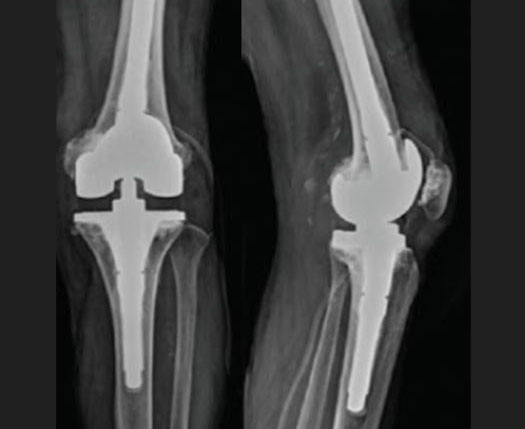

When a knee replacement fails, treatment depends on the cause of failure. Each case is unique and if there is more than the usual amount of bone loss extra pieces of metal or bone are added during revision knee replacement.

When infection is the cause for failure of knee replacement, removal of the infected implants and eradication of the infection is done in first stage. After an interval of 6 to12 months a second procedure i.e second stage revision knee surgery is done.